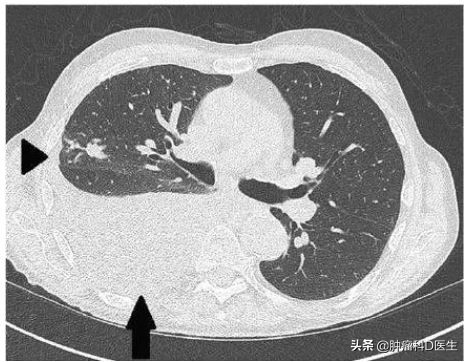

恶性胸腔积液可以通过X线、CT、超声显示;胸腔穿刺引流获得标本;细胞学病理确诊

CT下的胸腔积液和被压缩的肺